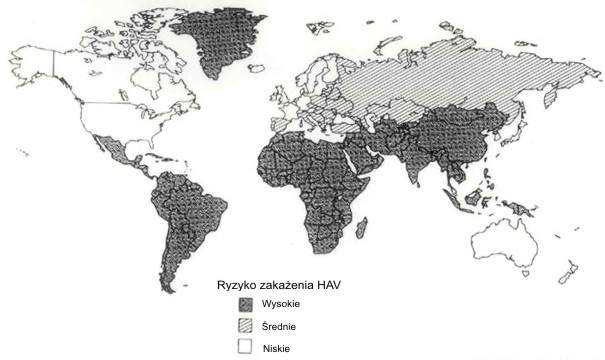

Wirusowe zapalenie wątroby typu A, zwane popularnie "ŋóģtaczką pokarmową", jest to szeroko rozpowszechniona na ķwiecie choroba zakažna wywoģywana przez wirus HAV (Hepatitis A Virus), uszkadzający komórki wątrobowe. Rocznie notuje się od 1,2 do 1,4 miliona przypadków, ale przypuszcza się, ŋe występuje 3-10 razy częķciej. Szacuje się, ŋe WZW A stanowi ponad 50% wszystkich wirusowych zapaleņ wątroby. W krajach, w których występują zģe warunki sanitarne, rozwija się w zbiorowiskach: ŋģobkach, przedszkolach, szkoģach, domach dziecka, ķrodowisku domowym. Bardzo wysoką zapadalnoķæ notuje się w krajach Afryki, Azji Poģudniowo-Wschodniej, Ameryki Poģudniowej. Największa na ķwiecie epidemia wystąpiģa w 1988 roku w Szanghaju. Zachorowaģo wówczas ponad 300 000 osób, Ģatwoķæ z jaką zakaŋenia HAV szerzą się w ķrodowisku wynika z opornoķci wirusa na wiele czynników zewnętrznych np.: na kwas octowy, fosforowy, chloroform, eter, związki fenolu i alkohole. HAV jest natomiast wraŋliwy na dziaģanie formaliny oraz kwasu solnego. Ginie natomiast w autoklawie w temperaturze 121 st.C po 30 minutach oraz pod wpģywem gotowania przez pięæ minut i promieniowania UV. W temperaturze od -20 st.C do +4 st.C HAV zachowuje stabilnoķæ przez wiele lat. Wysuszony w temperaturze pokojowej lub znajdujący się w wodzie, owocach morza i ķciekach jest zdolny wywoģywaæ zakaŋenie przez wiele tygodni. W procesie pasteryzacji mleka w temperaturze 60-63 st.C ulega unieszkodliwieniu dopiero po dziesięciu godzinach. Czģowiek jest jedynym rezerwuarem HAV i žródģem zakaŋenia. Zaraŋają się nim gģównie maģe dzieci, które chorują subklinicznie. Opisywane byģy róŋne warianty genotypowe. Od ludzi chorych na WZW A wyizolowano genotypy I, II, III i VII. Pozostaģe genotypy są patogenne dla maģp i nie mają wpģywu na sytuację epidemiologiczną WZW A.

- podróŋujących do krajów o wysokiej zapadalnoķci na WZW A (np. Tunezja, Egipt)